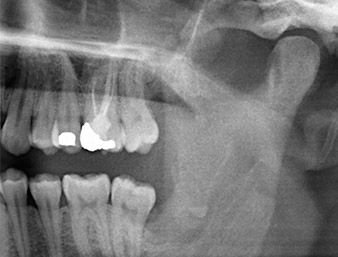

À l’OPG, le reste radiculaire dans la région de la dent 38 (LL8) apparaît déjà très proche du nerf alvéolaire inférieur. La racine s’est fracturée pendant l’ostéotomie mais n'a pas été extraite par le prestataire de soins primaires en raison de douleurs peropératoires. Pour minimiser le traumatisme causé aux tissus, la nouvelle ostéotomie devait être réalisée par piézochirurgie. Le patient ne présente pas d’antécédents médicaux particuliers et est non-fumeur.

OPG 6 mois après l’ostéotomie

Fig. 1 : OPG 6 mois après l’ostéotomie de la dent 38 (LL8) : la racine résiduelle est proche du nerf alvéolaire inférieur.